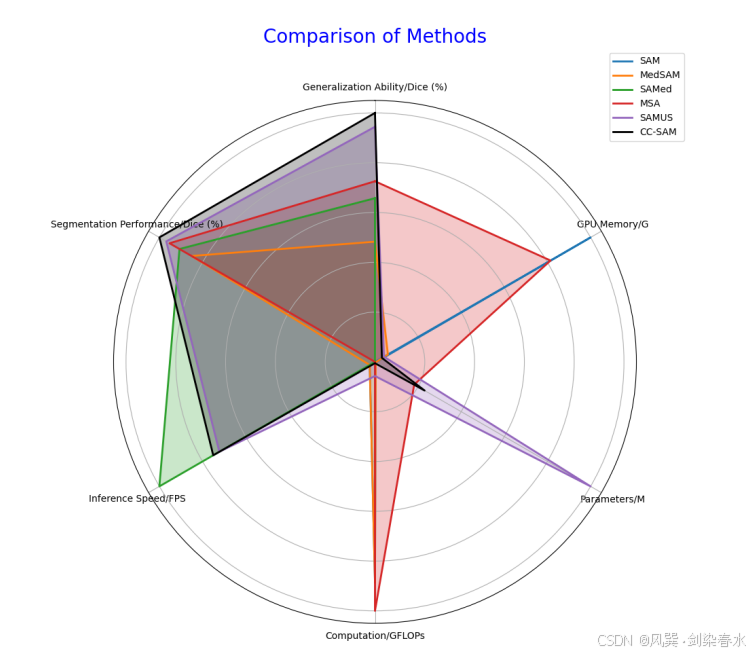

Figure 8 | 蜘蛛图,与所有基础模型比较效率和分割性能: